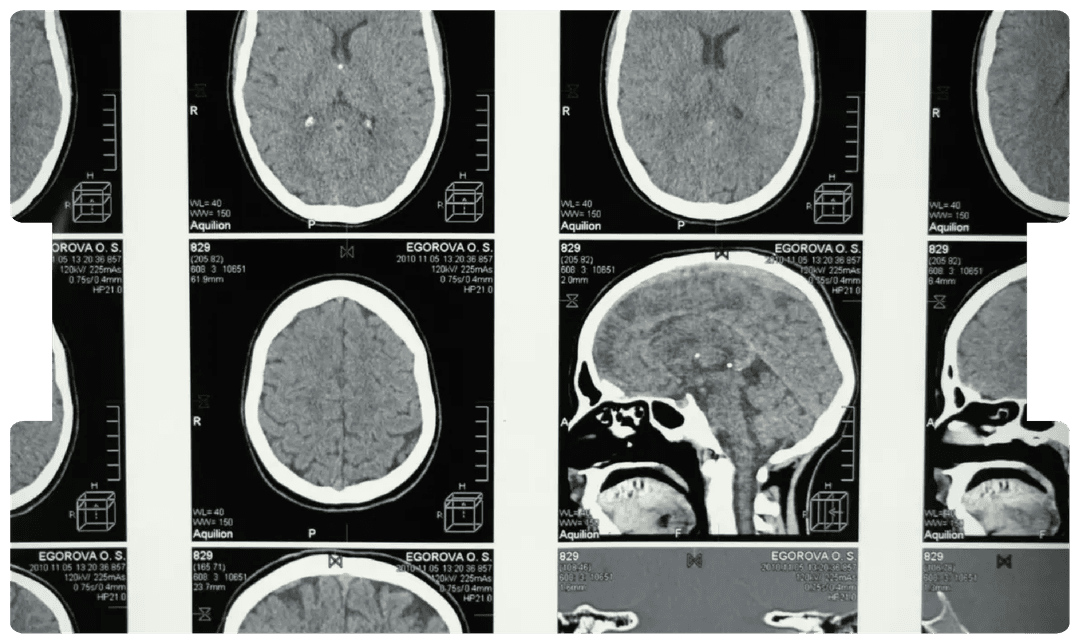

Acoustic Neuroma and Medical Negligence

- Acoustic Neuroma

- Delayed Diagnosis